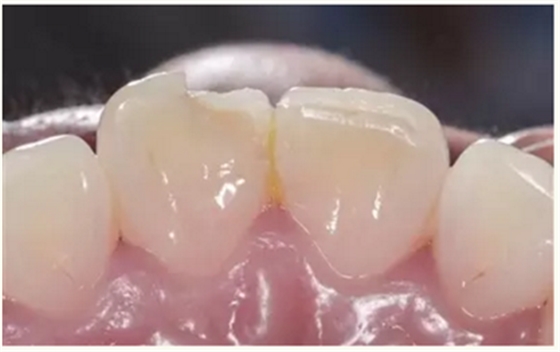

牙体树脂美学修复适用于对牙体修复效果有美学要求的前牙或者后牙。对于患者而言,前牙修复效果更为直观。因此,临床上对于前牙美学修复的需求更为迫切,常见的修复类型为及切角的前牙牙体缺损。治疗的过程一般为①比色、②缺损牙体的树脂预修复(直接修复)或者取模翻制石膏模型的基础上制作蜡型恢复缺损牙体(间接修复),③硅橡胶制作舌侧导板,④上橡皮障,牙体预备(洞缘斜面),⑤酸蚀、粘结,⑥树脂分层充填,⑦修形、抛光,⑧完成。

▲术前(唇侧)

▲术前(舌侧)